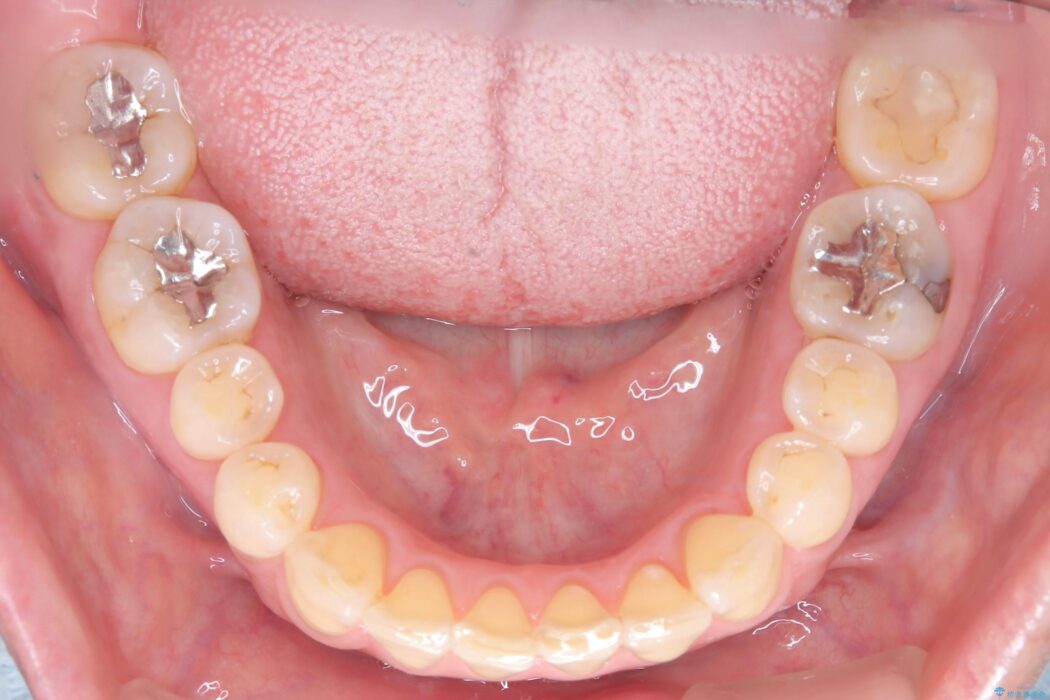

ワイヤー矯正ならではの確実な歯のコントロールにより、当初の計画通り約1年という短い期間で、前歯のガタつきが解消。見た目が美しく整っただけでなく、清掃しやすい機能的な歯並びを獲得していただけました。